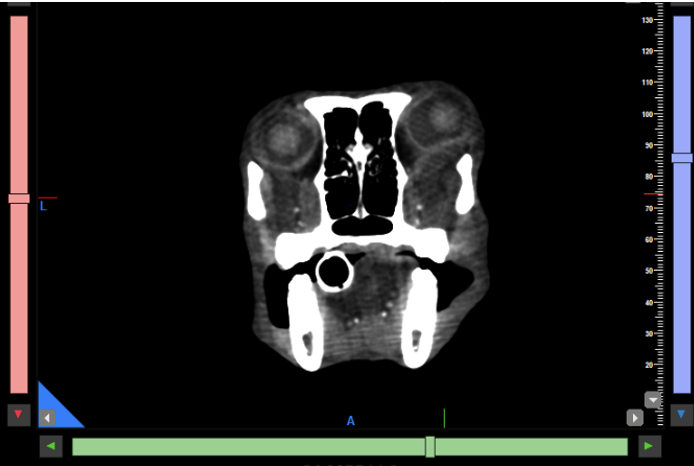

Kopf und Hals: Tumoren im und am Kopf lassen sich mit dem CBCT sehr präzise darstellen. Neben der exzellenten Beurteilung knöcherner Invasionen können auch Weichteilanteile zuverlässig abgegrenzt werden, was insbesondere für die präoperative Planung relevant ist. Kiefer- und Zahntumoren sowie komplexe dentale Erkrankungen profitieren weiterhin von der hohen Ortsauflösung des CBCT, die in diesen Bereichen einem klassischen Slice-CT überlegen sein kann. Bei brachycephalen Patienten hat sich das präoperative Dental-CT als Standard etabliert und ersetzt häufig eine Vielzahl konventioneller Dentalröntgenaufnahmen (Abb. 1 & 2).

Vergleichende Darstellung eines KI optimierten Kopfscans einer Katze mit einem destruktiven Tumor im Kopfbereich (links original, rechts KI gestützt).